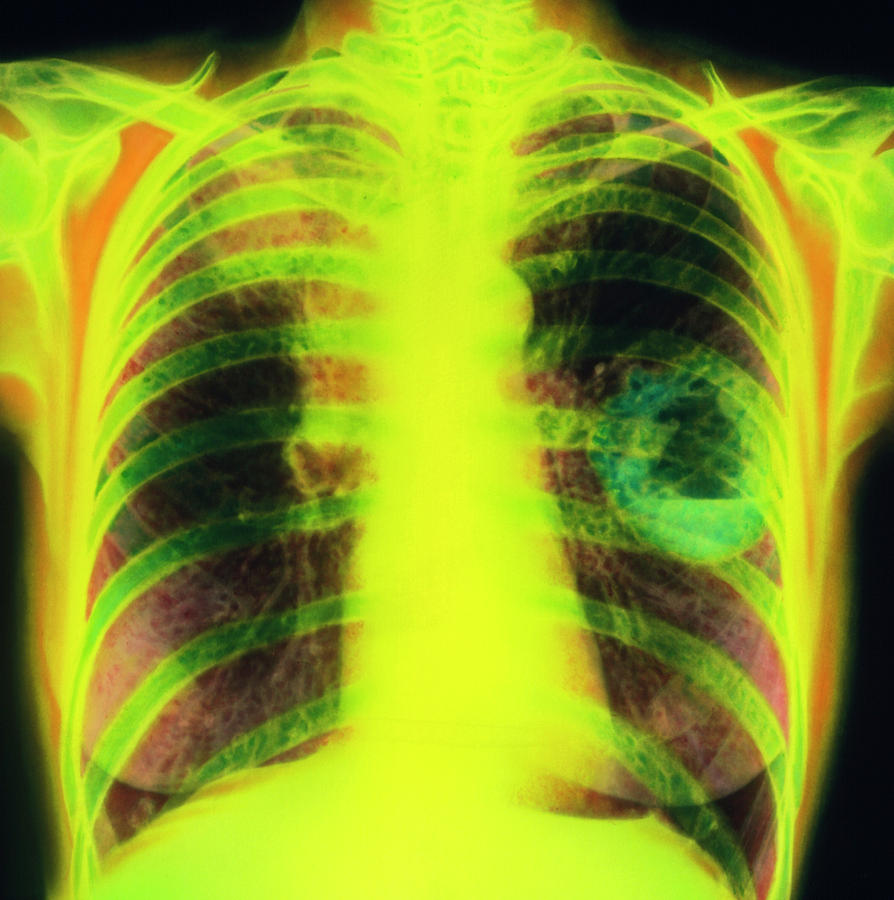

Lung Cancer Screening X Ray

Experience the clarity of Lung Cancer Screening X Ray with our curated collection of comprehensive galleries of images. featuring understated examples of photography, images, and pictures. designed to emphasize clarity and focus. Discover high-resolution Lung Cancer Screening X Ray images optimized for various applications. Suitable for various applications including web design, social media, personal projects, and digital content creation All Lung Cancer Screening X Ray images are available in high resolution with professional-grade quality, optimized for both digital and print applications, and include comprehensive metadata for easy organization and usage. Our Lung Cancer Screening X Ray gallery offers diverse visual resources to bring your ideas to life. Comprehensive tagging systems facilitate quick discovery of relevant Lung Cancer Screening X Ray content. Multiple resolution options ensure optimal performance across different platforms and applications. Time-saving browsing features help users locate ideal Lung Cancer Screening X Ray images quickly. The Lung Cancer Screening X Ray archive serves professionals, educators, and creatives across diverse industries. Instant download capabilities enable immediate access to chosen Lung Cancer Screening X Ray images. Whether for commercial projects or personal use, our Lung Cancer Screening X Ray collection delivers consistent excellence. Professional licensing options accommodate both commercial and educational usage requirements.